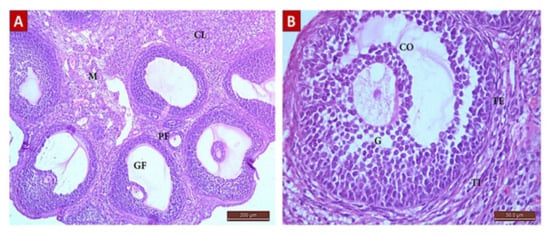

Diosmin 50 (Group III, Figure 6)

Diosmin 100 (Group IV, Figure 7)